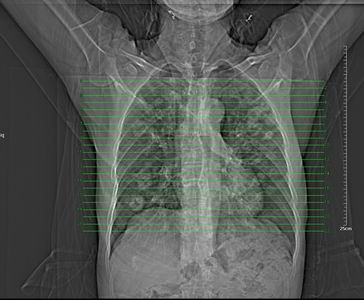

男 60岁,咳嗽,胸疼半年,请各位老师讨论.

肺内多发小结节,部分内见空泡,边界大部分清楚.多考虑:1 韦格氏肉芽肿.2 肺泡癌伴肺内转移不除外.

肺内多发结节样病灶,部分内见空泡影,边界大部分清楚,多考虑:

1.金葡菌感染

2 转移不除外

影像学表现:文献报告肺部浸润性见于50-65%的病人,肺部均有浸润,表现为肺内多发或单发结节影,出现多发厚壁空洞,内壁粗糙,易合并细菌性肺炎,也可出现胸腔积液。ct及hrct扫描可见大小不等的结节多分布于肺周边部,结节可呈楔形贴近胸膜,另一主要特征是其周围有线状斑痕影,即长毛刺征,受累血管及血管周围纤维化是其形成的原因,如累及胸膜尚可出现胸膜凹陷征。71%ct比胸片发现更多更小病灶, 典型的征象滋养血管征仅能在ct上显示。ct及hrct可检出典型影像征象。为诊断提供了重要依据,ct可成为肺韦格氏肉芽肿首选检查方法。